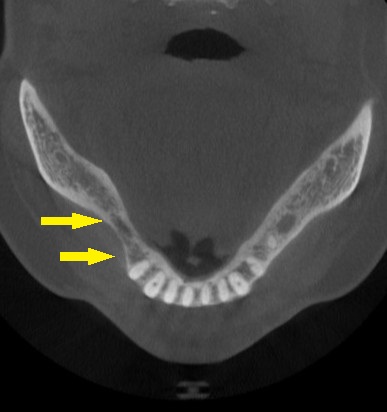

CTで見ると、歯肉がやせているのと同じように、骨も細くなってしまっていました(下の写真2段目)。

骨幅が狭いので、インプラント埋入と同時に、外側に人工骨を補填して、骨幅を増やす、骨造成術の併用が必要であると説明させていただきました。